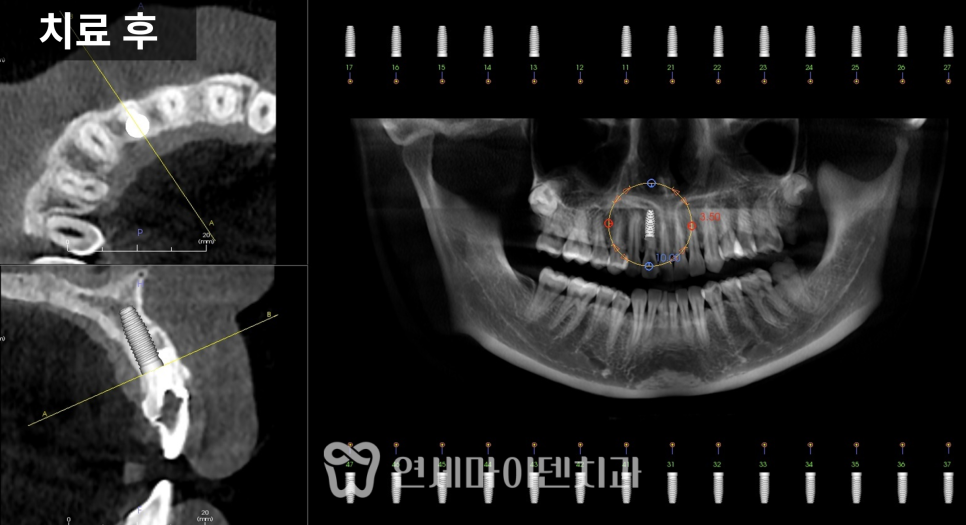

치료 전 방사선 사진을 보면

치아가 쓰러진 문제도 있었지만

무엇보다 뼈의 폭과 높이가

많이 줄어든 상태

였습니다.

1차 수술: 발치, 염증 정리, 식립과 이식 동시 진행

첫 단계에서는

아래 1개, 위 2개

3개의 임플란트를 계획했습니다.

위쪽은 상악동이 내려와 있어

상악동 거상술과 뼈이식을 함께 시행한 뒤

그 공간에 임플란트를 식립했습니다.

아래쪽은 뼈 상태가 비교적 유지되어 있었지만

안정적인 고정을 위해

필요한 부위에 뼈이식을 병행했습니다.